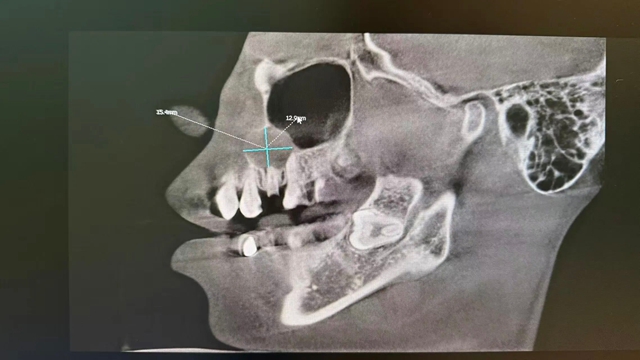

CBCT(三维口腔CT)影像检查显示:右上前磨牙残根的根尖位置,有一个直径约1.5cm×1.2cm的类圆形囊性阴影,边界清晰。囊肿与上颌窦腔之间仅隔着一层极薄的上颌窦壁,稍有不慎就可能导致口腔与上颌窦腔穿通,引发感染、口鼻漏等严重并发症。

术前“侦察”:依赖CBCT三维影像,医生能像拥有透视眼一样,看清囊肿的大小、范围、与重要结构(如上颌窦、神经)的距离,制定毫米级的手术方案。